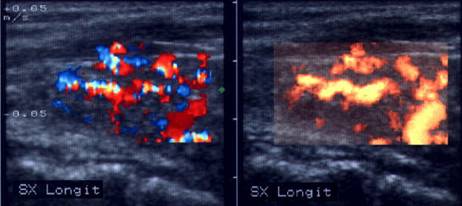

Acelasi caz. La doppler color - vascularizatie interna, mai evidenta in powerdoppler.

Apexul lobului drept, proiectie longitudinala si trasversala.